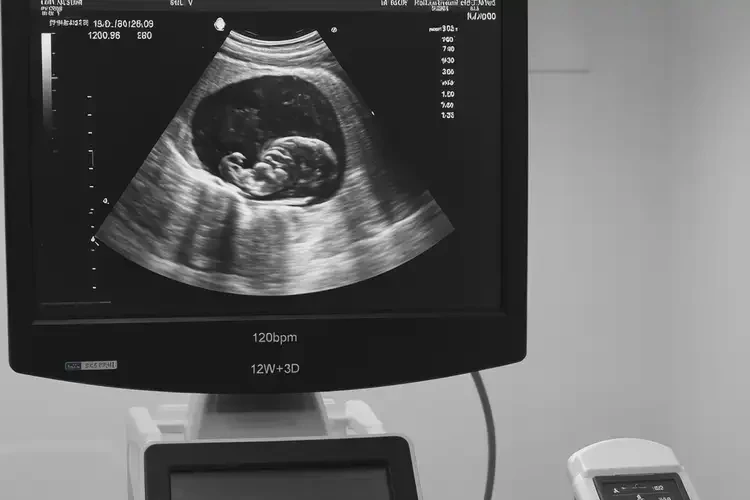

怀孕90天胎心90左右还能保住吗(图1)

2. 超声检查:通过超声检查可观察胎儿的发育情况、羊水量等。